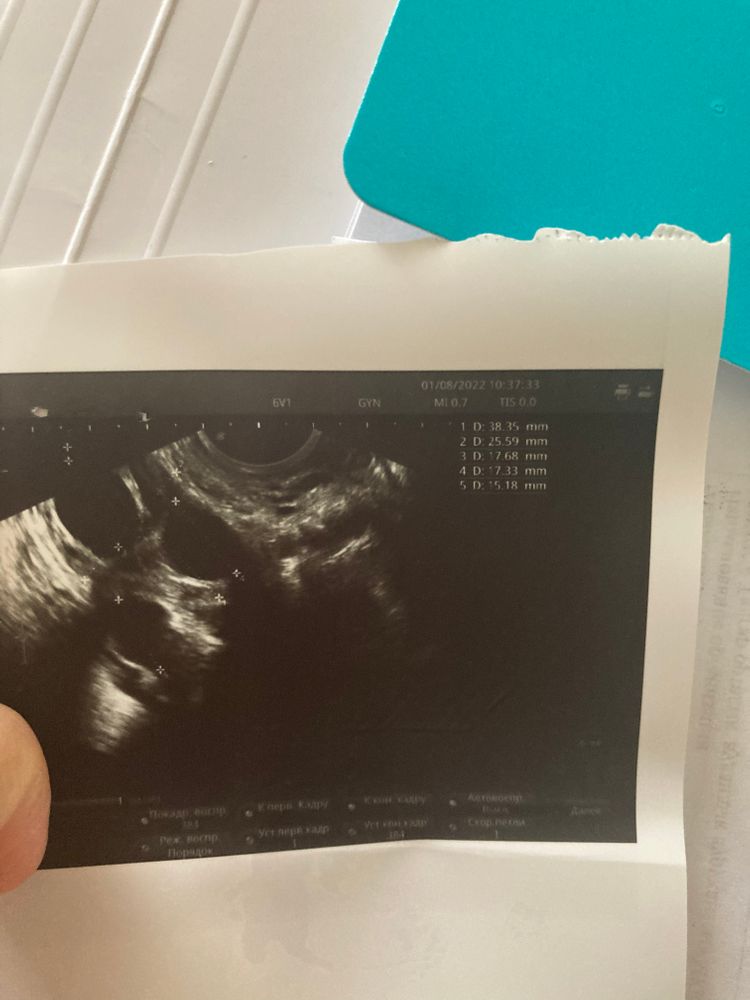

Сегодня 11 день цикла сходила на узи чтобы посмотреть как там яйчники мои и есть ли уже доминантный.

И вот тут пепец🥺😂 В левый яичник-4 Больших фолликул это уже Доминантный?

И в правый яичник-3 фолликул тоже большие …

У вас легкая гиперстимуляция яичников. ответили все фолликулы , доминанты нет. А вот эндометрий подкачал, Он должен быть 8-10 мм. Без укола ХГ 10.000 они не лопнут. А с 16 дня начинайте принимать Утрожестан, он будет способствовать росту эндометрия нормальной 2 фазы цикла